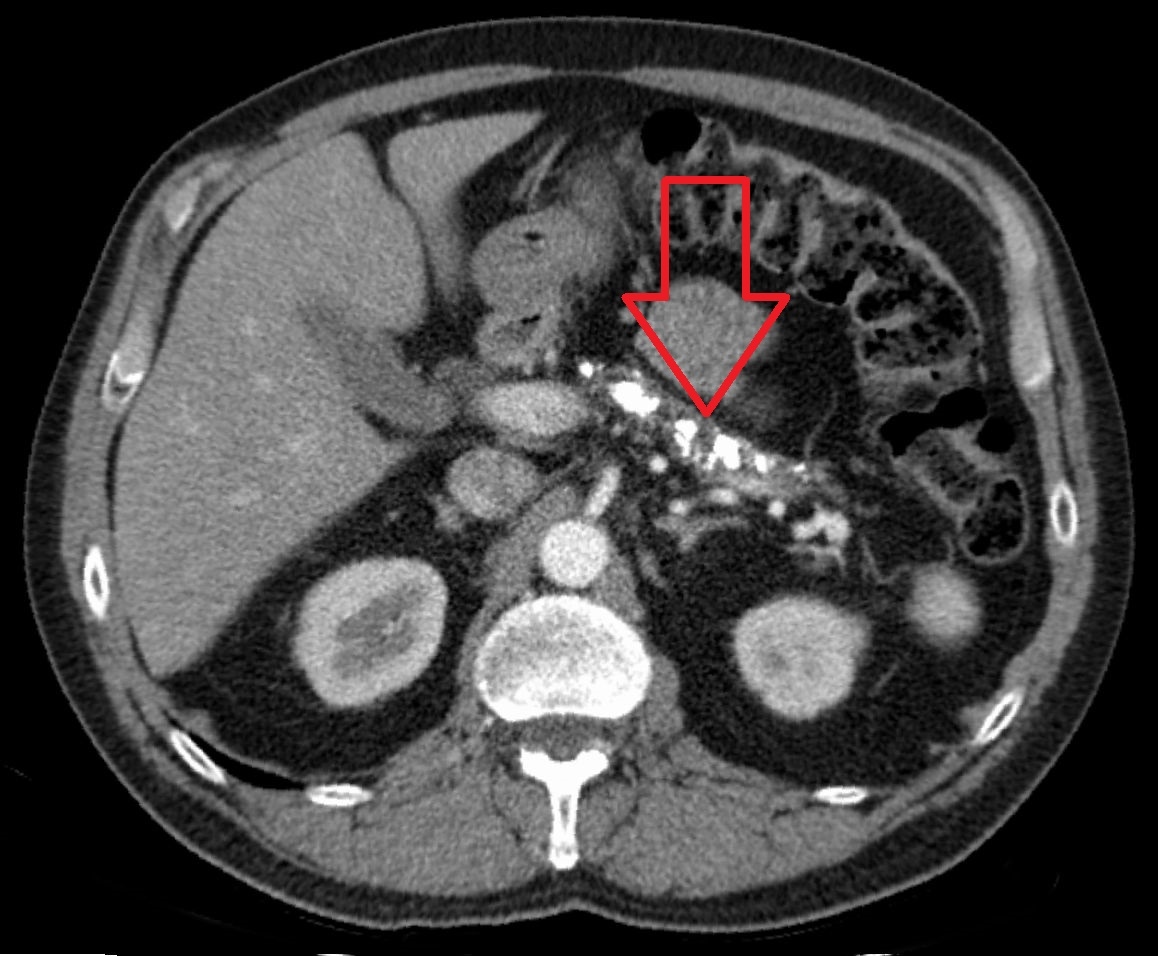

На КТ рак підшлункової залози (найчастіше аденокарцинома) зазвичай виглядає як зона нижчої щільності (гіподенсивна) проти оточуючої тканини. В окремих випадках пухлина може бути ізоатенюючою, і для діагностики важливим стає аналіз непрямих ознак: дилатація панкреатичного протоку ("обрізання"), атрофія тканини залози дистальніше від пухлини, збільшення жовчного протоку. Критерієм неоперабельності є навколосудинне залучення — оклюзія або захоплення судин більш ніж на 180°.

Одне з ключових призначень КТ — визначення операбельності пухлини. Оцінюється ступінь інвазії в основні судини: черевну аорту, ворітну вену, верхню брижову вену. Операбельними вважають пухлини, які не охоплюють судини більш ніж на 180° (без оклюзії), без віддалених метастазів і значних лімфовузлових змін. КТ відіграє вирішальну роль у прийнятті рішення про хірургічне лікування і відборі кандидатів.

Поразка лімфатичних вузлів проявляється їх збільшенням (>1 см), зміненою формою чи ішемічними ознаками. Метастази у печінку на КТ виглядають як вузли зниженої щільності. Тромбоз ворітної вени прямо впливає на вибір лікування.